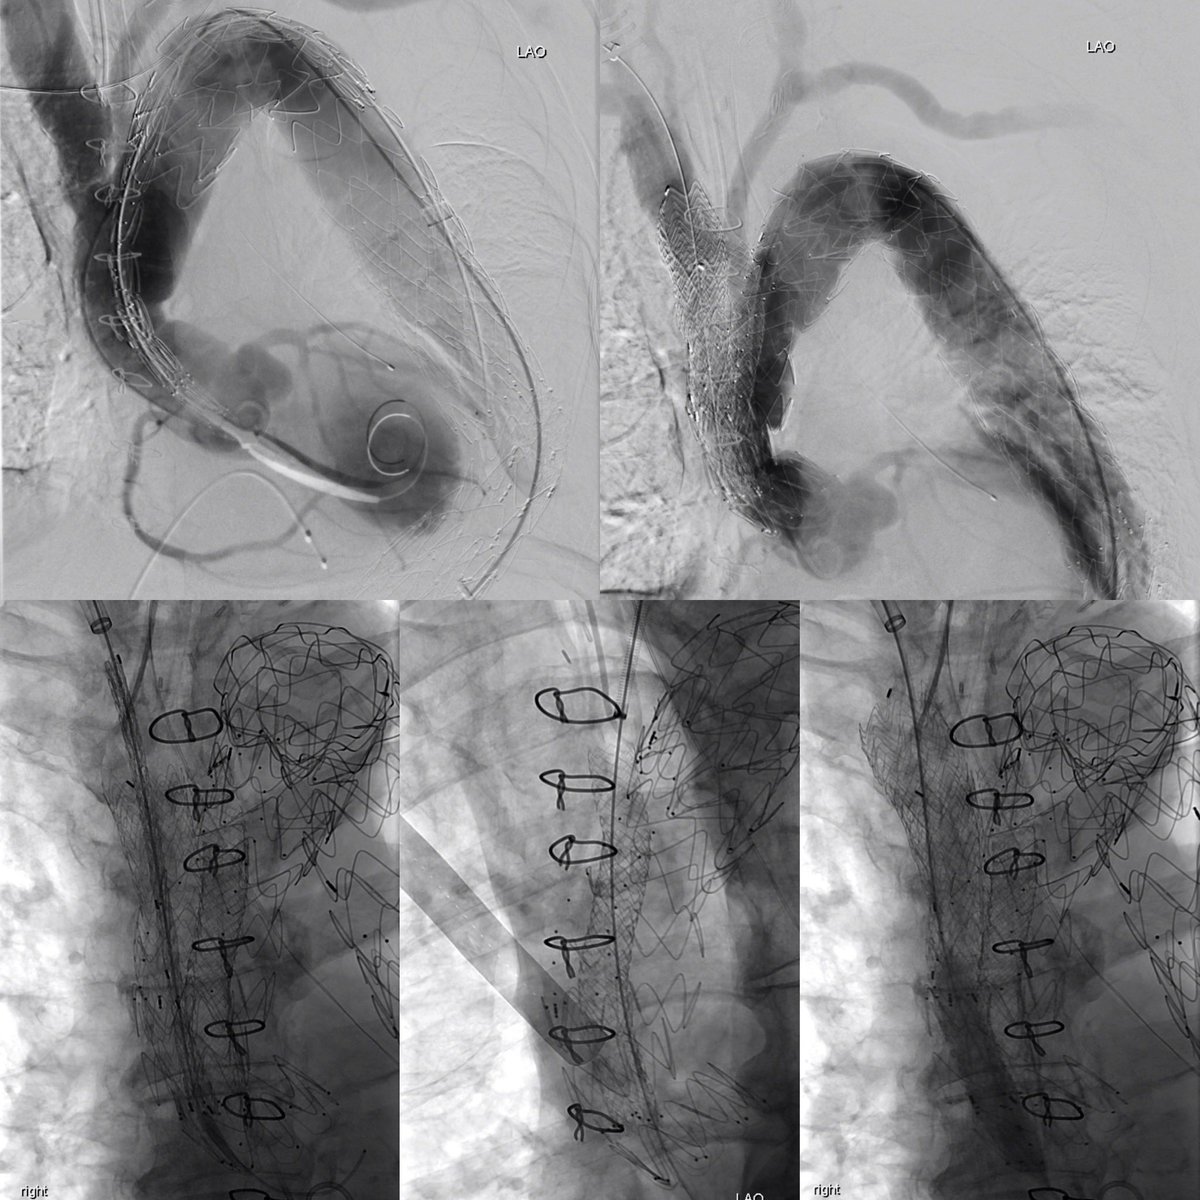

TBAD with rapid growth. Treated on D25 post event. Circumferential delamination in the perivisceral segment. Treated with #PETTICOAT @CookMedical @CAIRweb @anastasiah04